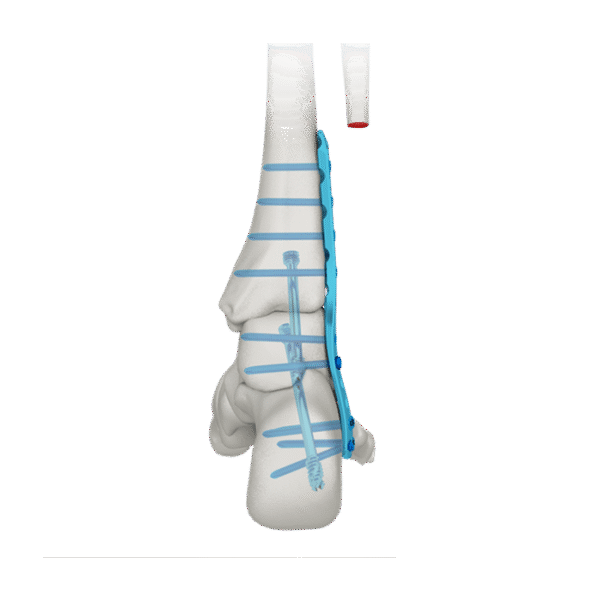

- Tres filas de orificios en el extremo distal, para fijar el calcáneo; Tornillo de fijación divergente, para mejorar la buena sujeción.

- Tres filas de agujeros en el medio, para fijar el astrágalo; tornillo de fijación divergente, para proporcionar una fijación estable

- Diseño de perfil bajo, para reducir la irritación de los tejidos blandos.

- Fusión de la articulación tibiotalar

- Fusión de tibiotalar lateral y calcáneo